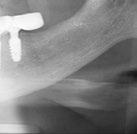

la derecha debida a la asimetría ósea detectada al inicio del tratamiento. En la figura 34 se muestran los cambios producidos por el tratamiento ortopédico-ortodóncico realizado, con la mejoría de casi todos los valores cefalométricos analizados, así como los ángulos de la convexidad (160 º), nasolabial (100 º) y mentolabial (118 º) más cercanos a la norma.

Las cinco áreas de las superposiciones se visualizan en la figura 35 . Se puede apreciar el crecimiento del mentón y la mejoría en las relaciones dentarias y el perfil.